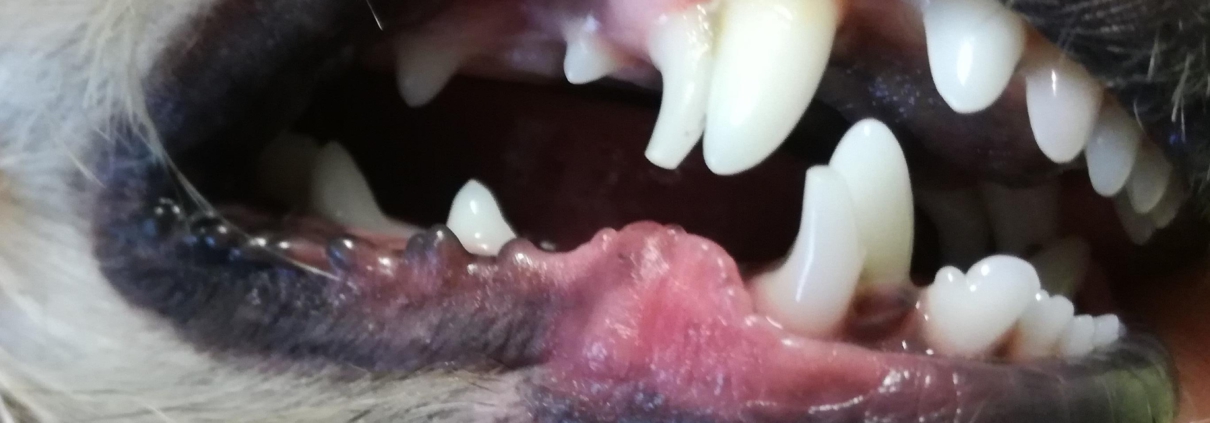

Zahnbehandlungen

- Ultraschallzahnsteinentfernung, Politur nach Zahnreinigung

- Zahnextraktion

- Beratung und Vorsorge Zahnerkrankungen